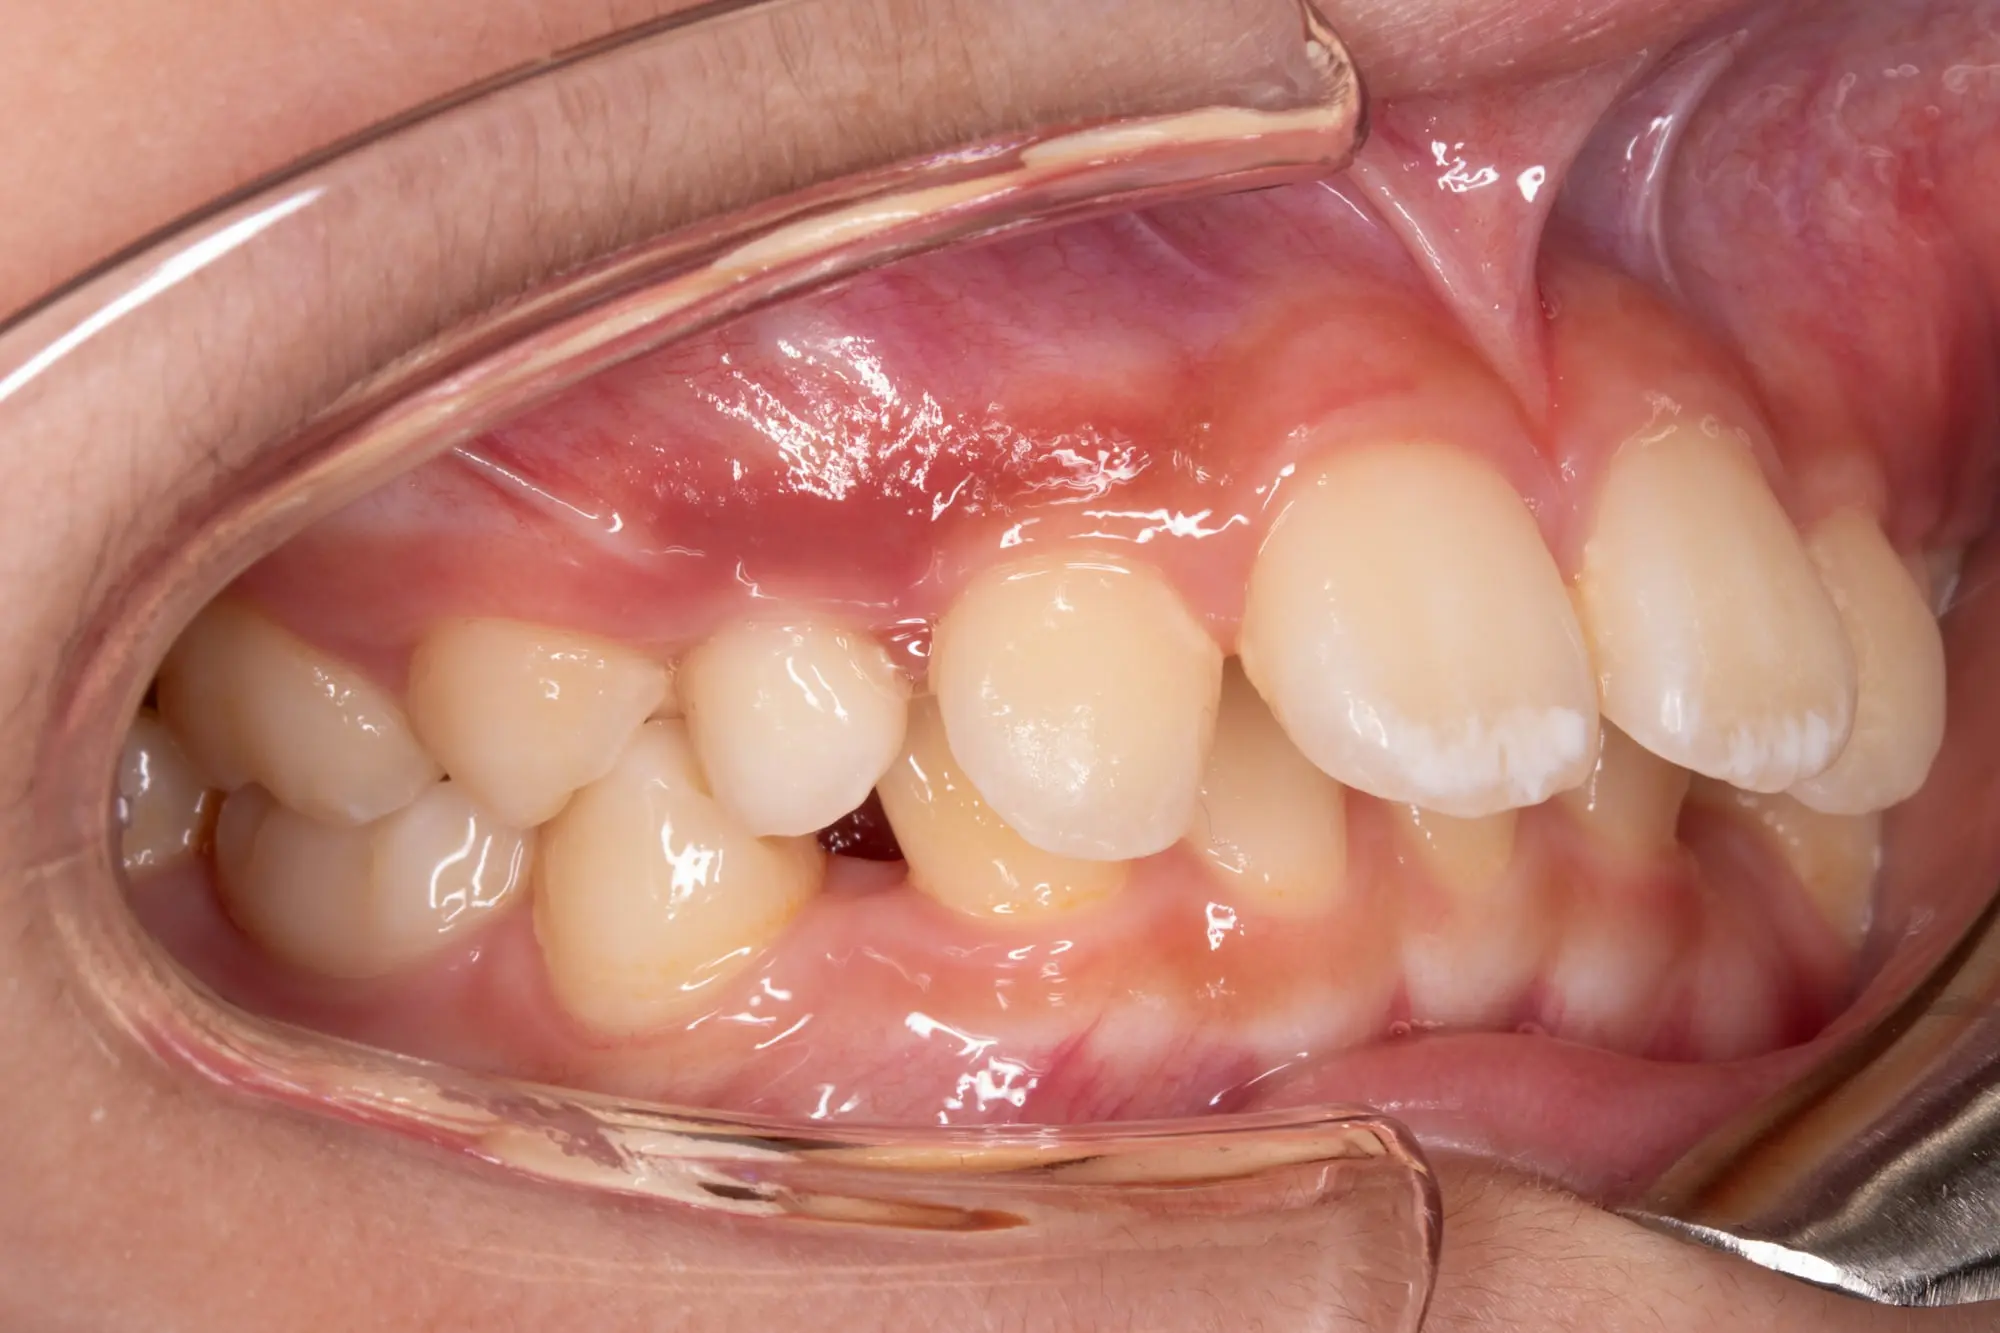

Before

After

Flared Teeth